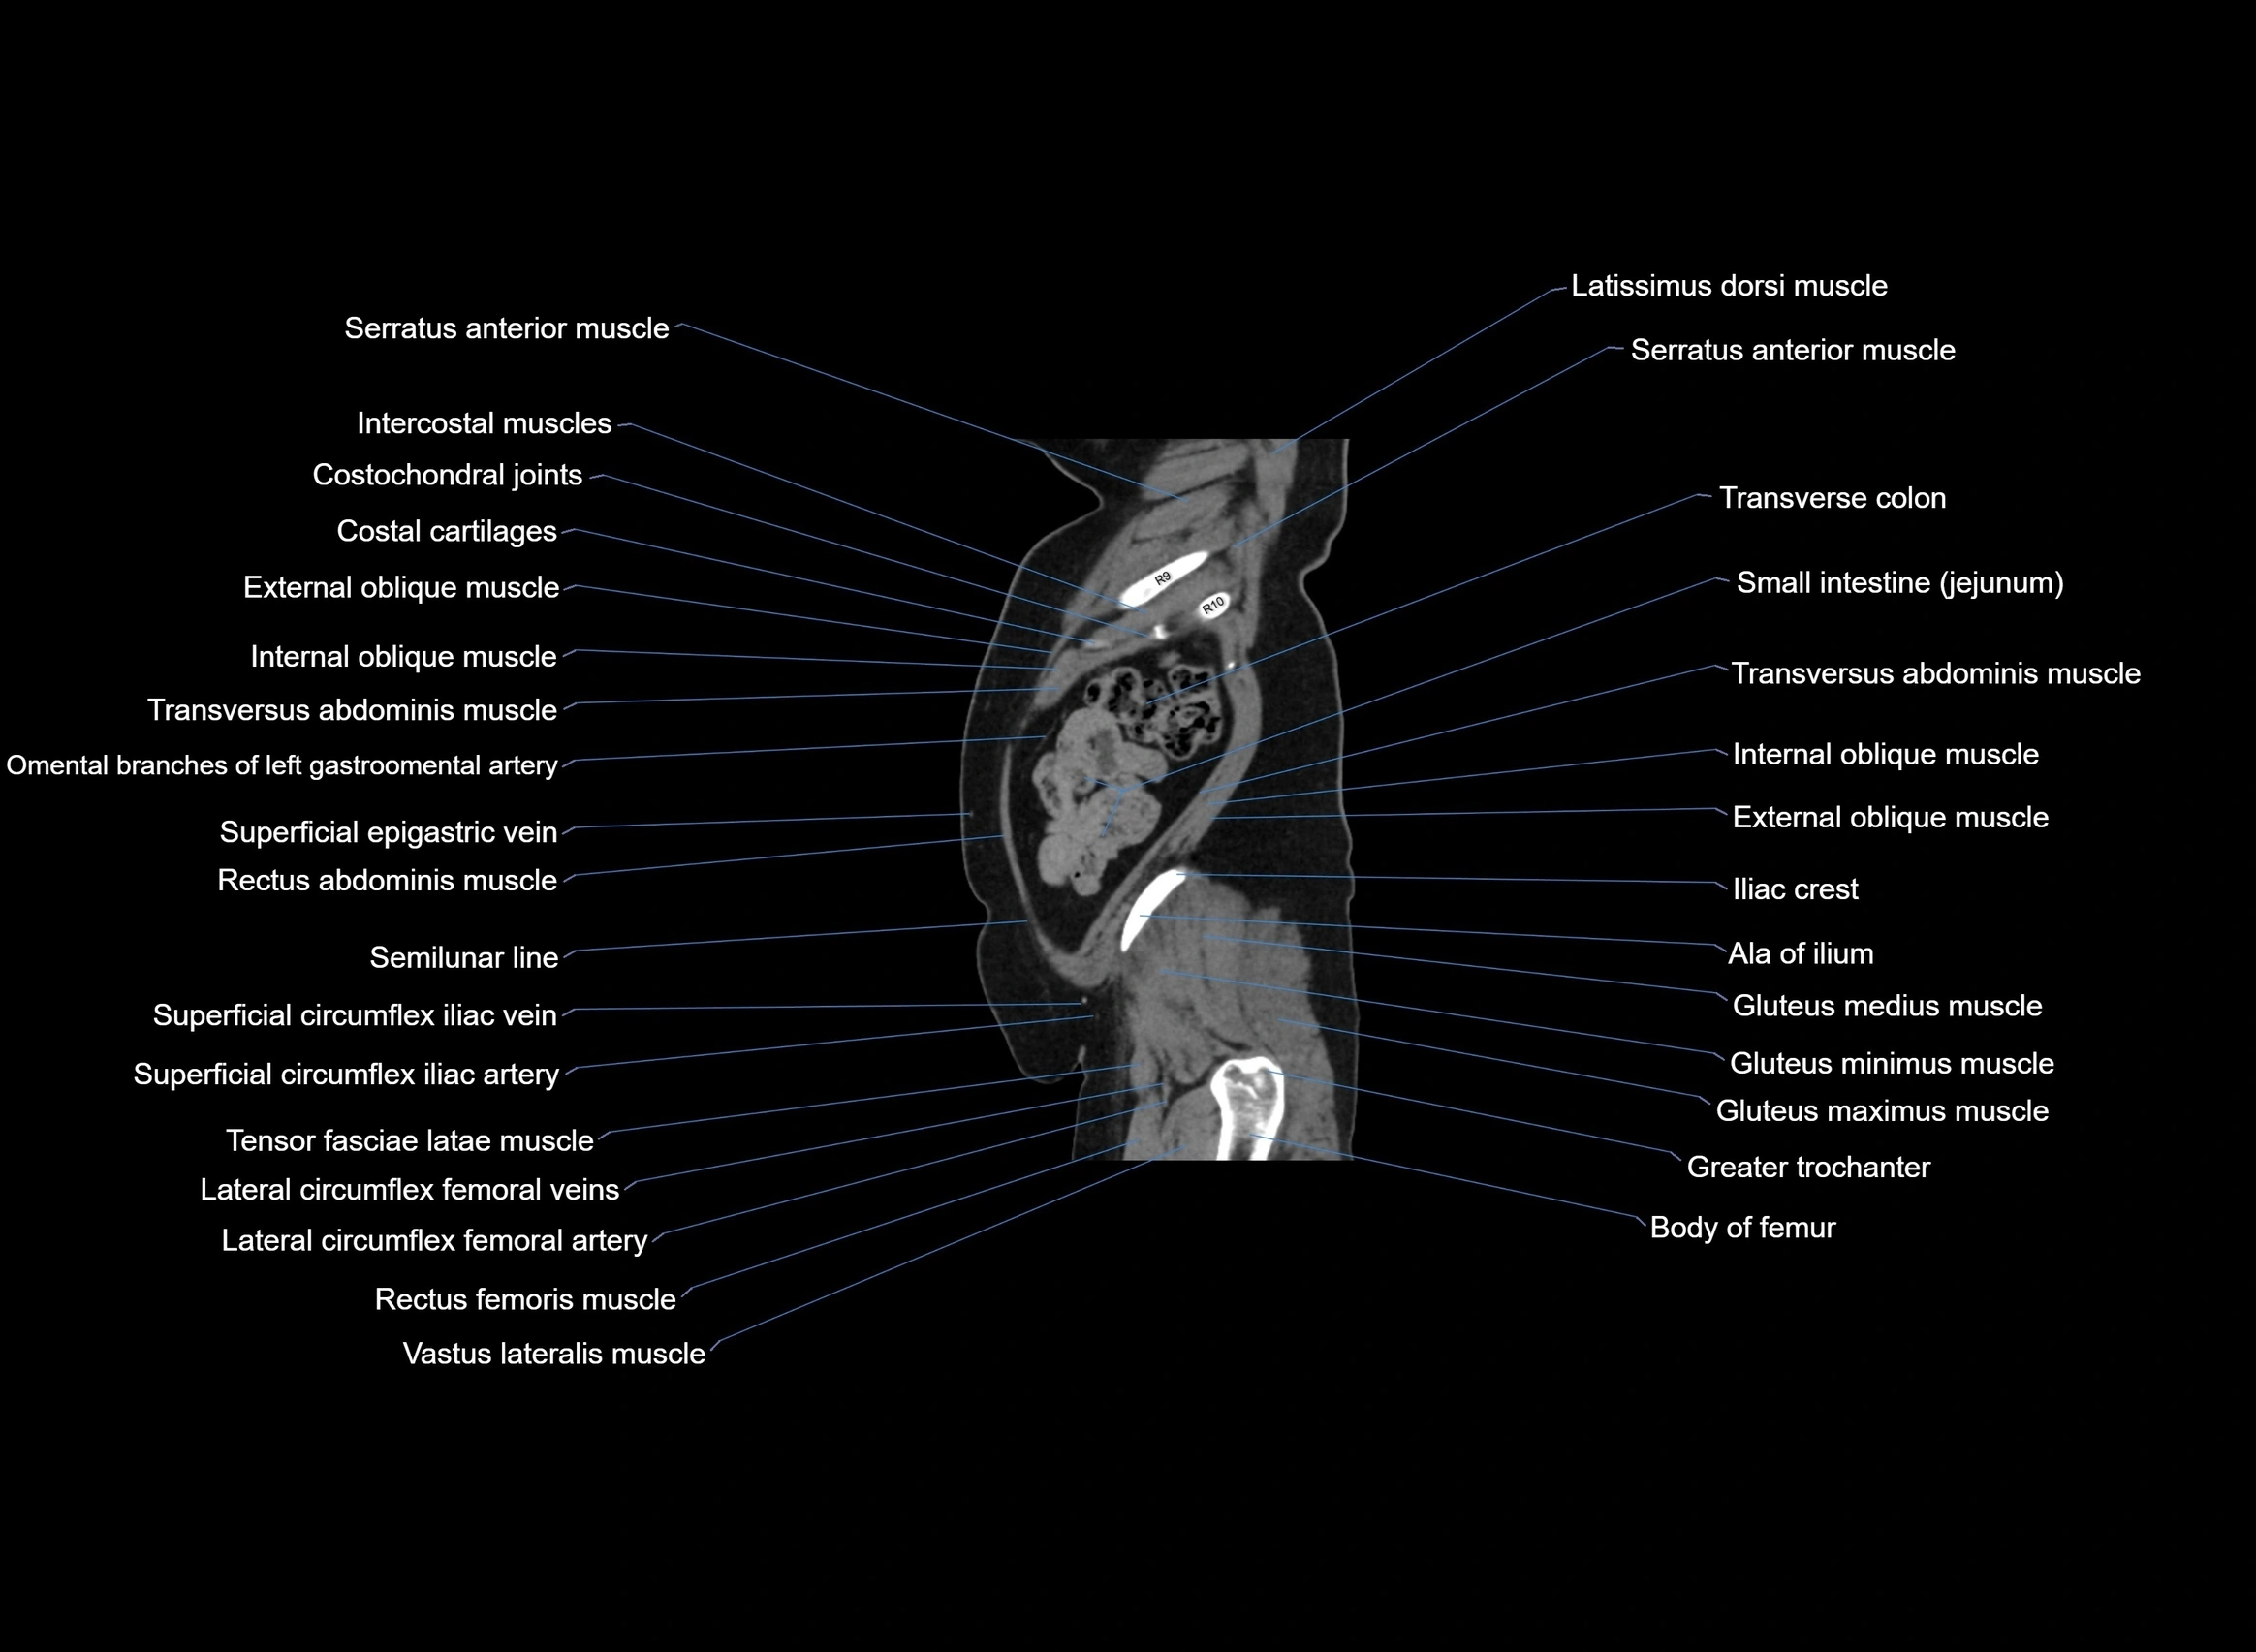

- Iliac crest

- Latissimus dorsi muscle

- External oblique muscle

- Internal oblique muscle

- Transversus abdominis muscle

- Rectus abdominis muscle

- Rectus femoris muscle

- Vastus lateralis muscle

- Tensor fasciae latae muscle

- Gluteus minimus muscle

- Gluteus medius muscle

- Gluteus maximus muscle

- Greater trochanter

- Body of femur

- Lateral circumflex femoral artery

- Lateral circumflex femoral veins

- Superficial circumflex iliac artery

- Superficial circumflex iliac vein

- Iliotibial tract